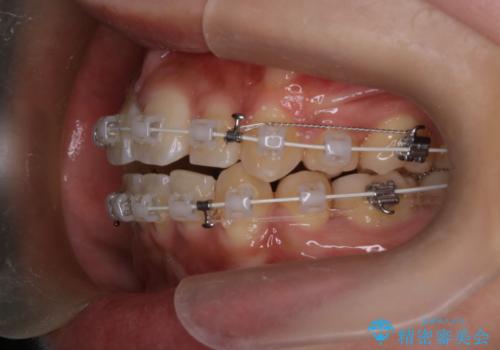

- 前歯の突出が強く、口元が前に出ている印象を改善するため、上下左右の第一小臼歯(4番)を抜歯する矯正治療を計画しました。抜歯により得られたスペースを利用して、前歯を後方へと移動させて整列します。治療には目立ちにくい透明な審美ブラケットとワイヤーを使用し、毎月1回の調整を行いながら徐々に歯を動かし、約2年で口元全体を整える計画としました。

前歯が前に出ているため口元が突出し、唇が閉じにくいなどの悩みを抱えておられました。治療にあたり上下左右の第一小臼歯を抜歯し、十分なスペースを作ることで前歯を効果的に後方へ移動させました。装置には透明で目立ちにくい審美ブラケットを採用し、治療中の審美的ストレスを軽減しました。定期的な調整を通じて無理なく確実に歯列を整え、前歯の突出感を解消。治療後は口元の印象が自然で美しく改善され、患者様には非常にご満足いただけました。